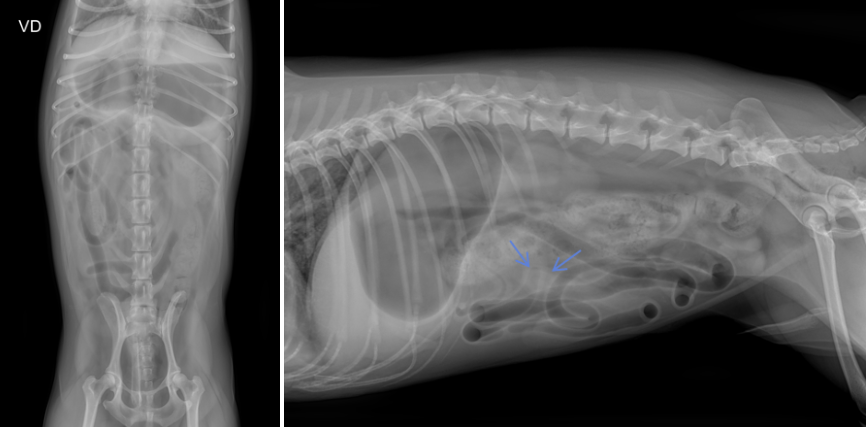

이럴 때는 기계적 폐색(이물로 인한 장 막힘) 여부를 확인하기 위해 접근성이 좋고 신속하게 진행할 수 있는 복부 방사선(X-ray) 검사를 먼저 시행하는 것이 일반적입니다.

하지만 방사선 검사는 이물 진단의 민감도와 특이도가 약 66% 수준으로 단독으로는 정확도가 높지 않습니다.

실제로 이 환자의 경우, 방사선상 씨앗 형태의 이물로 의심되는 희미한 음영이 관찰되었으나 음영이 뚜렷하지 않았고 소장의 명확한 확장 소견도 확인되지 않아 단순 방사선만으로는 이물에 의한 폐색을 확정하기 어려운 상황이었습니다.

따라서 이런 경우에는 복부 초음파 검사를 추가로 시행하여 이물 자체의 위치와 형태, 장벽의 두께 변화, 장 운동성, 폐색 부위 전후의 확장 정도 등을 평가함으로써 진단의 정확도를 높이는 것이 필요했습니다.